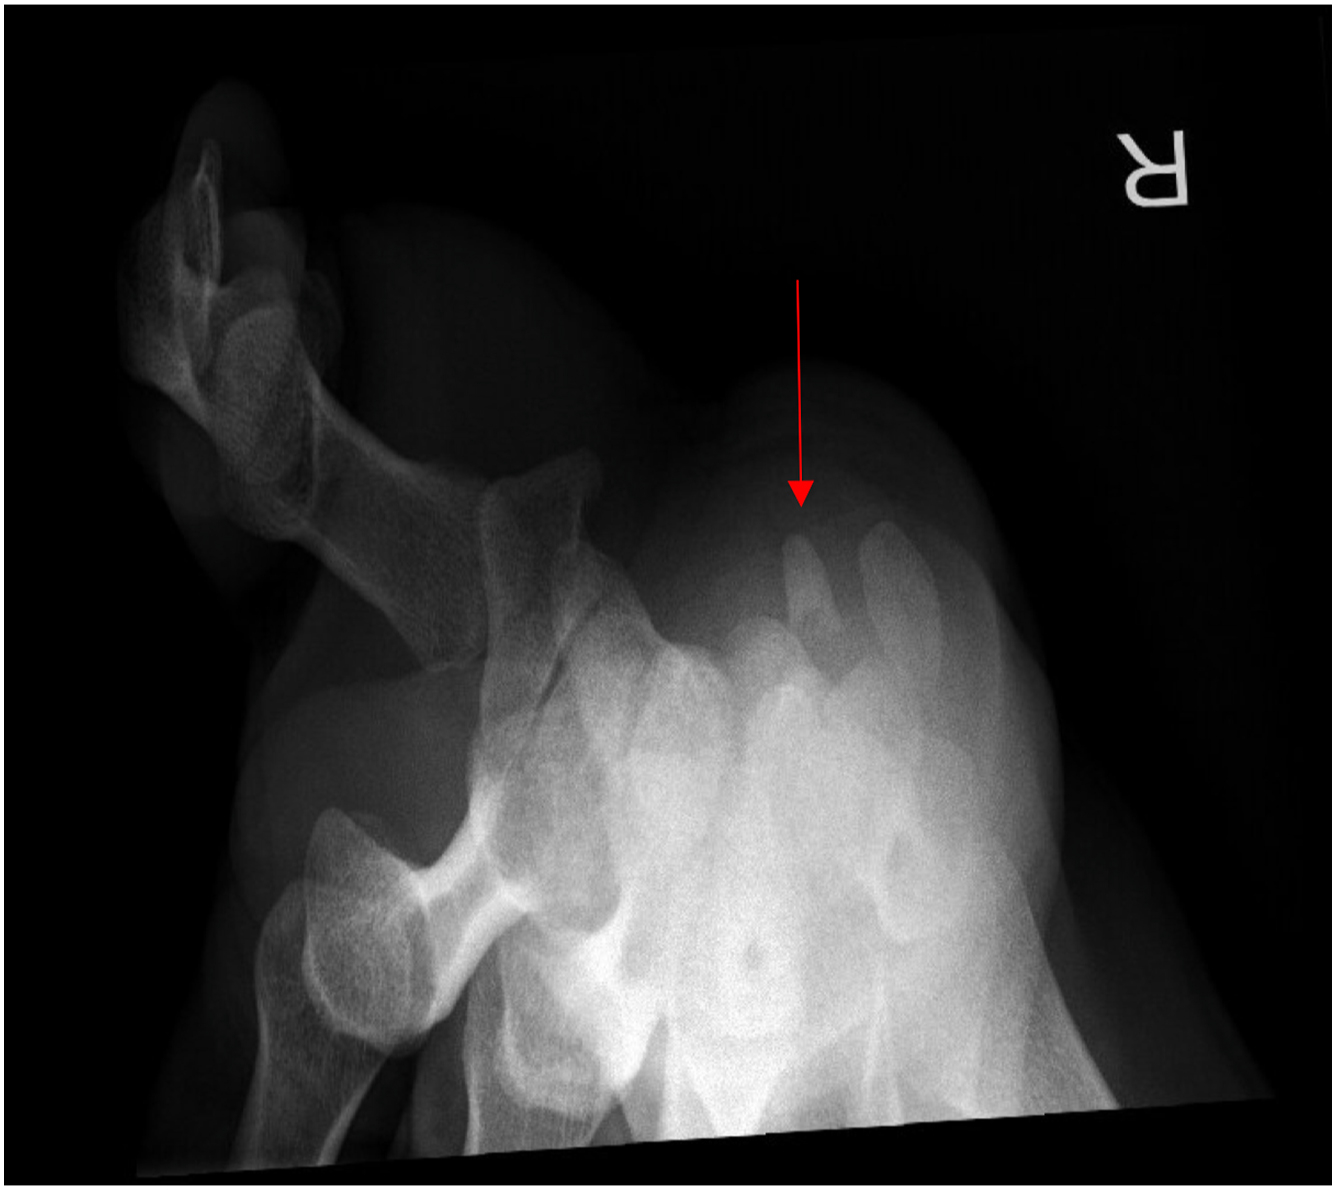

The hook of hamate pull test, described by Wright and colleagues, can be used to further increase the examiner’s suspicion for a hook of hamate fracture. The test is considered positive if pain is encountered with resisted flexion of the ring and small fingers with the wrist placed into ulnar deviation. Suspicion of this injury, however, should be confirmed with standard radiographs and advanced imaging. Posteroanterior (PA), lateral, and oblique views of the wrist may not reveal the fracture. Thus, a carpal tunnel view can be performed if tolerated by the athlete ( Fig. 1 ). The gold standard of diagnosis is the computed tomography, with an accuracy of 97.2% compared with 80.5% for pain radiographs (including all projectional planes). MRI can be used if neurovascular injury or flexor tendon injury is suspected ( Fig. 2 ).